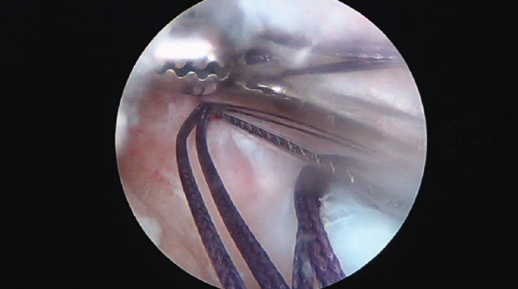

En esta ocasión, se indicó una cirugía de rescate del LCA con tendón cuadricipital y tenodesis extraarticular lateral (TEL) (Vídeo 1). Se realizó la cirugía bajo anestesia general, con el paciente en posición de decúbito supino con isquemia femoral y la rodilla flexionada 90°. Se realizaron los portales artroscópicos transtendinoso y anteromedial, a través de los cuales se objetivó el estado intraarticular de la rodilla, encontrándose los restos del menisco interno en aparente correcto estado y una lesión crónica del LCA. Seguidamente, se realizaron: un abordaje anterior sobre el tendón cuadricipital, extrayéndose un injerto de 10 mm de grosor con pastilla ósea de 2 cm; y un abordaje lateral para la preparación del injerto de fascia lata mediante disección de una tira central de 7 mm de grosor manteniendo la inserción distal de la misma. Ambos injertos fueron envueltos en una solución de vancomicina durante 10 minutos(3). Mientras tanto, se realizaron los túneles para ambas plastias: tras eliminar los restos del LCA, en primer lugar, se colocó la aguja guía del túnel femoral con una guía estándar de túnel tibial (Stryker Endoscopy, Kalamazoo, EE. UU.) abierta 70°, en dirección fuera-dentro, utilizando como entrada extraarticular un punto inmediatamente proximal y posterior al epicóndilo lateral, y como punto de salida intraarticular el centro de la inserción anatómica del LCA. A continuación, se colocó la aguja tibial en dirección fuera-dentro, con punto de salida sobre la huella anatómica del LCA, posterior a la raíz anterior del menisco medial y medial a la del lateral. Posteriormente, se realizó cada túnel con una broca de 10 mm en dirección fuera-dentro y se limpiaron los bordes del túnel de restos de partes blandas. Dado que el túnel femoral de la cirugía primaria se había realizado en posición muy vertical y que el túnel tibial se había realizado en posición muy posterior (presumiblemente se realizó una técnica transtibial), ninguno de los túneles de la cirugía de rescate, colocados en posición anatómica, interfería con la plastia previa y las huellas anatómicas femoral y tibial fueron fácilmente reconocibles en este caso. En primer lugar, se realizó el pase del injerto para la TEL bajo el ligamento colateral lateral (LCL) y a través del túnel femoral en dirección fuera-dentro, extrayendo los hilos de tracción a través del portal artroscópico anteromedial. Seguidamente, se realizó el paso del injerto de LCA con tendón cuadricipital en dirección fuera-dentro y caudocraneal a través del túnel tibial hacia el túnel femoral. Una vez en su sitio correspondiente, se realizó la fijación de los injertos mediante tornillo interferencial (Biosteon® 10 × 35 mm; Stryker Endoscopy, Kalamazoo, EE. UU.), comenzando por el extremo tibial y, posteriormente, con la rodilla flexionada 30°, terminando por el extremo femoral (Biosteon® 10 × 28 mm, Stryker Endoscopy, Kalamazoo, EE. UU.), donde el mismo tornillo se utilizó como fijación de las plastias de LCA y TEL.

Vídeo 1. 1: exploración artroscópica de la rodilla; rotura de la plastia del LCA, meniscectomía medial previa y degeneración en compartimento medial; 2: abordajes para extracción de injertos (tendón cuadricipital y fascia lata); 3: colocación de las agujas y perforación de los túneles femoral y tibial en dirección fuera-dentro; 4: limpieza de restos de cartílago y ligamento; 5: distancia entre la inserción de la plastia primaria y la huella anatómica, donde irá insertada la plastia de rescate; 6: introducción del injerto de fascia lata bajo el ligamento colateral lateral e introducción en dirección fuera-dentro en el túnel femoral; 7: paso del injerto de tendón cuadricipital; 8: fijación de los injertos; 9: comprobación de la correcta tensión del injerto de LCA.